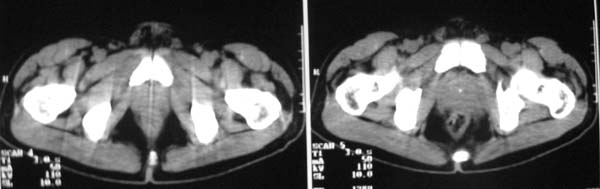

以下是引用zjzjr在2007-9-27 22:20:00的发言:[br]肠腔受推移,未见明显扩张及液平,所以考虑是肠外病灶, 间叶源性肿瘤?脂肪瘤?建议增强。

以下是引用guzhongliangddd在2007-9-27 23:21:00的发言:[br][br]与肠内高密度相同,病灶应该没有钙化,我认为首先考虑是间叶组织的良性肿瘤。建议楼主做后重建观察。中线区域大血管旁未见确切增大淋巴结。病灶对肠道只是推移关系。

以下是引用余辉在2007-9-27 22:24:00的发言:[br]暂考虑肠道间质来源肿瘤如小肠平滑肌肉瘤/瘤可能,应该增强